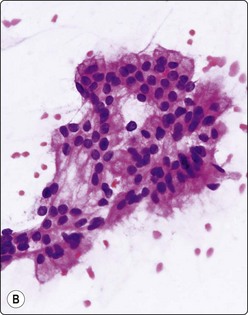

image image

Fig. 11.11 Adenocarcinoma (pancreas) moderately differentiated

(A) Sheets showing disorganization and nuclear pleomorphism; background of necrotic debris (H&E, IP); (B) Disorganized clusters with some acinar arrangements (MGG, HP).

Almost all adenocarcinomas arising in the pancreas are of ductal origin, without unique features permitting absolute distinction from carcinomas arising in the biliary tree. The characteristic FNB pattern is of crowded ‘drunken’ monolayered sheets, with moderately tall columnar palisading cells at luminal edges. Smaller aggregates commonly show rounded glandular structures with feathered edges, or three-dimensionality. Cytoplasmic borders may be very well demarcated in better-differentiated forms; in other cases, the monolayer sheets appear syncytial. The diagnosis of malignancy ultimately depends on nuclear features, which range from very subtle alterations to overly malignant criteria with decreasing differentiation (Figs 11.9-11.11). In an assessment of individual criteria by regression analysis, Cohen and colleagues extracted as most important: anisocytosis (4 : 1), nuclear enlargement and molding, with combined sensitivity of 98% using all three criteria to distinguish malignant from benign.70 In a similar study, Robins, Katz and Evans ascribed major status to nuclear crowding, contour and chromatin irregularity, minor status to single cells, mitoses and enlarged nuclei,33 requiring two major, or one major and two minor criteria for the definitive diagnosis of malignancy. Focusing specifically on the most challenging area, the recognition of well-differentiated carcinoma, Lin and Staerkel listed the following features: nuclear enlargement > 2 rbc (99%), anisonucleosis 4 : 1 (97%), nuclear membrane irregularity (97%), and crowding/overlapping/three-dimensionality (92%).73